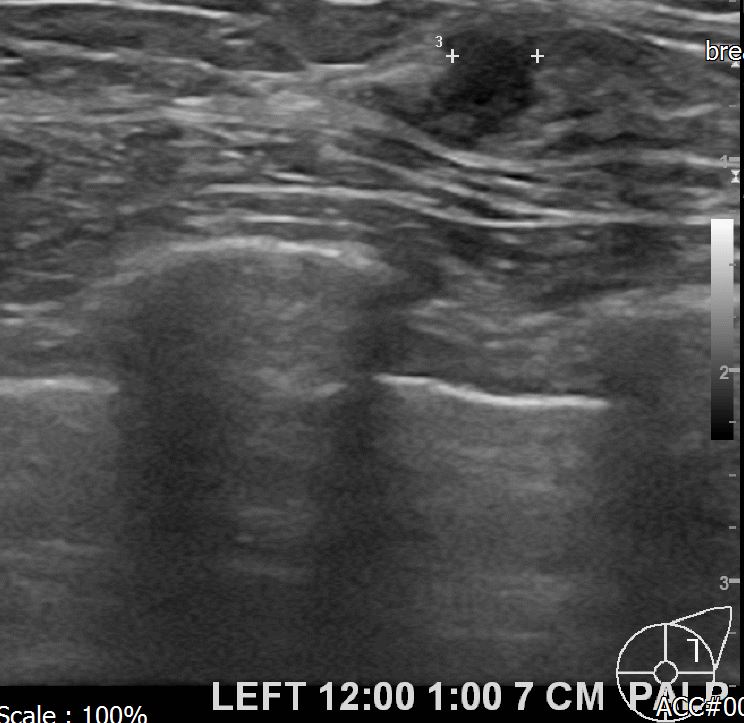

상기환자 좌측의 유방의 만져지는 멍울있어 내원하신40대후반의 여성분으로

초음파시행후 의심스런혹 조직검사후 유방암으로 진단되었습니다